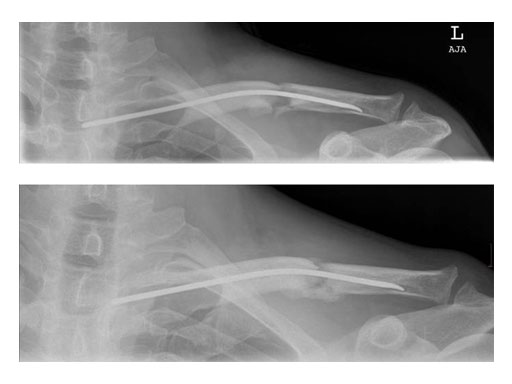

Case 1: Male, 56 years, Bicycle accident

Case 2: 51 years, male, hit by tree